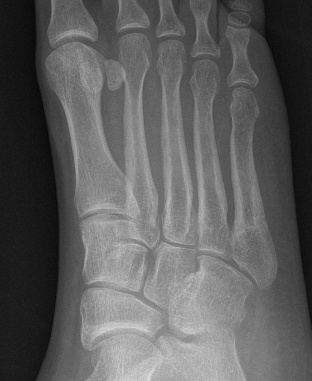

Xray

Zone 2 fractures

Union of zone 2 fracture with nonoperative care

Progression to nonunion of zone 2 fracture with nonoperative care

Zone 3 Fractures

Progression to nonunion of zone 3 fracture with nonoperative care

Torg Classification

| Type I | Type II | Type III |

|---|---|---|

| Acute | Delayed union | Nonunion |

|

Narrow fracture line No sclerosis No cortical reaction No periosteal hypertrophy |

Increased fracture line Both cortices Some sclerosis Some periosteal hypertrophy |

Significant sclerosis Significant cortical hypertrophy |